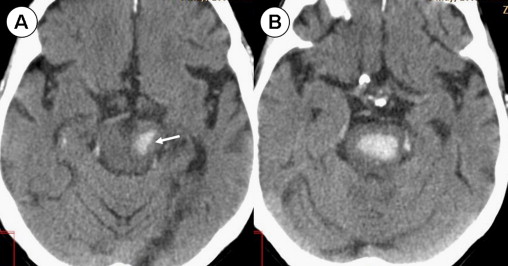

Picture this: six weeks postpartum, fit as a fiddle, no vices to speak of. I’d never smoked, rarely sipped, and my cholesterol was so pristine you could frame it. Doctors poked and prodded, shrugged their white-coated shoulders, and declared it cryptogenic—a fancy word for “beats us.” Just one of those cosmic pratfalls, like tripping over your own shadow mid-stride. No warning, no fault, just a brain misfiring while I was still catching my breath from new-mom life.